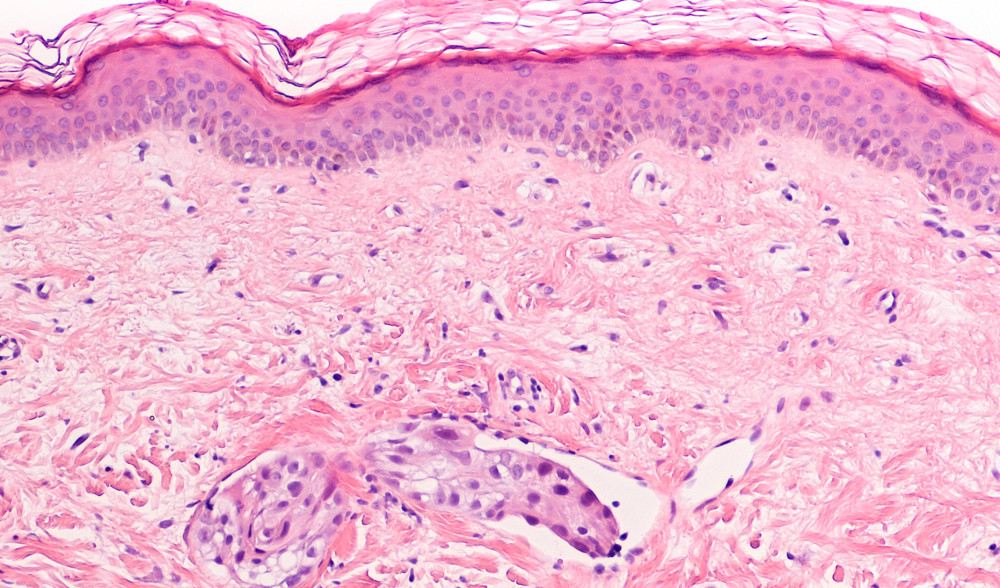

Analizzate più 2 mila pazienti

Questa scoperta“ci conferma che vincere la scommessa sulle staminali del cancro significa probabilmente vincere la scommessa contro la malattia” spiega Pier Giuseppe Pelicci, Direttore della Ricerca IEO, Professore all’Università statale di Milano e referente dello studio.